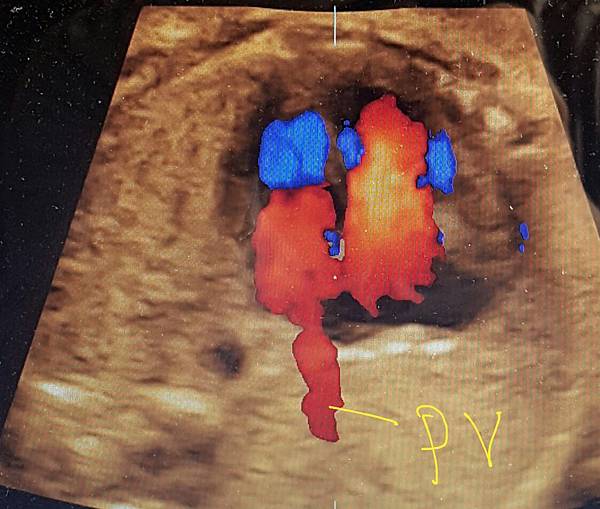

2016年10月10日,日本川瀧醫師(Dr Kawataki)在台灣的胎兒心臟超音波 stic seminar(附圖 9.10.)演講時講到一句話,flow and gray scale 同時看肺靜脈進入左心房才不會漏掉肺靜脈回流異常,他一語道破這個眉角,我是花了很多年才得到這個心得,如果川瀧再來台灣,我們要多跟他學習,他是一位有赤子之心的醫師,聽他的演講可以節省很多摸索的時間。